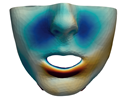

3.3. Simulation Error and Performance

4.1. Analysis of Simulation Accuracy

- Chin. Overall, the amount of error at the chin area is very low. This could be explained by the fact that the skin at the chin is very thin, and the coupling to the mandible makes the simulation highly predictive.

- Lips. In other regions, such as the lips, skin slides strongly over the underlying bones and teeth, and the deformation result is more difficult to predict. Overall, we observe higher variability in the error at the lips, and also some patients with higher error.

- Nose. The quality of the prediction of the deformation of the nose varies strongly across patients. In this case, the variability may depend on the type of surgery performed on each patient’s anterior nasal spine. This type of surgery is not easy to identify in the post-operative CBCT image due to the presence of bone grafts or fixation plates.

- Neck. Finally, we observe large error in the neck area (e.g., patients M5 and M8), and specifically at the junction point between the submental area and the neck (“C point” or “cervical point” in cephalometric analysis). This error was accounted for in our quantitative analysis, which negatively biased the overall results. However, this area is not of special interest to orthognathic surgeons. The deformation is known to be produced by a retraction of skin after surgery, but surgeons do not account for this effect during pre-operative planning.

- Segmentation of the maxilla and mandible. For all patients, the highest error (except for the neck, which is not clinically relevant as discussed above) appears near the cut areas, both of the maxilla (e.g., patients M5 and M7) and the mandible (e.g., patients M1 and M3). This is probably due to the presence of fixation plates and/or bone grafts in the real result (e.g., patient M10, whose maxilla was not segmented, but where the presence of bone graft has been confirmed by the surgeon who carried out the intervention). As a consequence, patients with a segmented maxilla and/or mandible show in general larger error than those without segmented bones. However, the smooth coupling method proposed in Section 2.3.3 reduces considerably the error in cut areas, as shown in Figure 2.